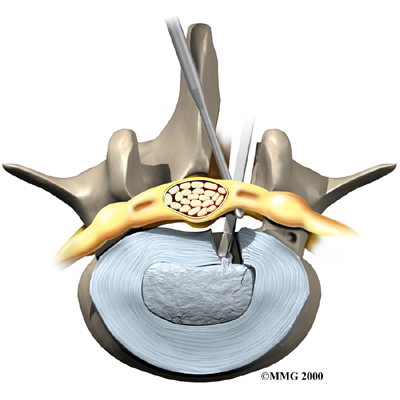

Microdiscectomy

Microdiscectomy is becoming the standard surgery for lumbar disc herniation. The procedure is used when a herniated disc is putting pressure on a nerve root. It involves carefully taking out part of the problem disc (discectomy). By performing the operation with a surgical microscope, the surgeon only needs to make a very small incision in the low back. Categorized as minimally invasive surgery, this surgery is thought to be less taxing on patients. Advocates also believe that this type of surgery is easier to perform, that it prevents scarring around the nerves and joints, and that it helps patients recover more quickly.